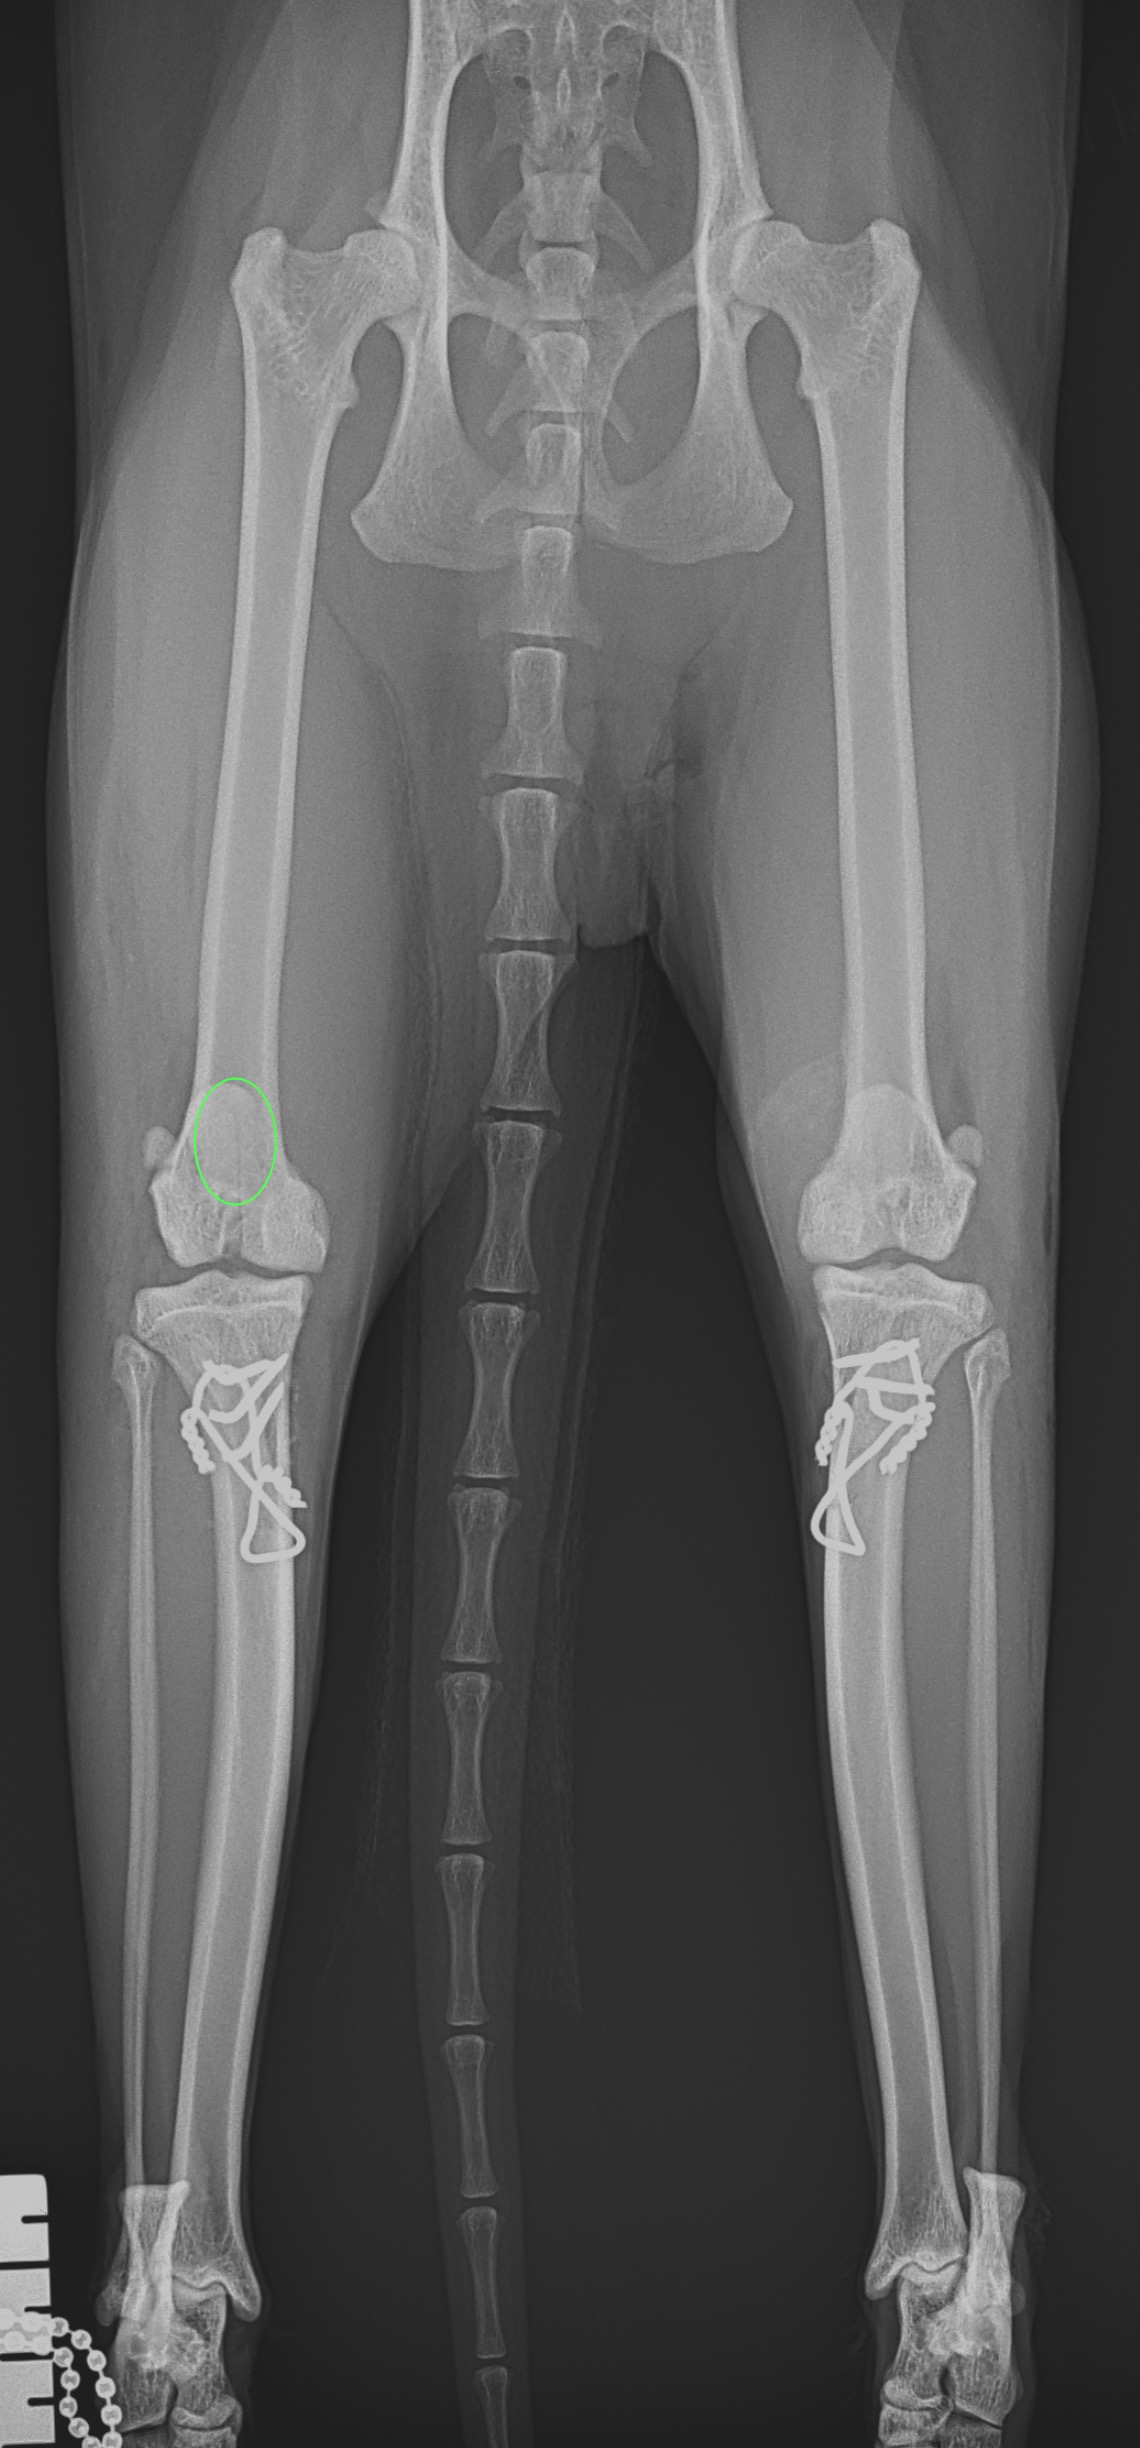

猫も犬と同様に膝蓋骨の問題は起こります。習慣性の膝蓋骨脱臼による異常なメカニカルによる負荷が関節軟骨に生じています。外科的に大腿骨滑車深化術、脛骨粗面移行術によるアライメント手術を行います。また、内科療法としてPRP:自己多血小板血漿を関節内に投与、レーザー照射、カルトロフェン・ベット、NSAIDs、アンチノールなどのサプリメントを継続します。